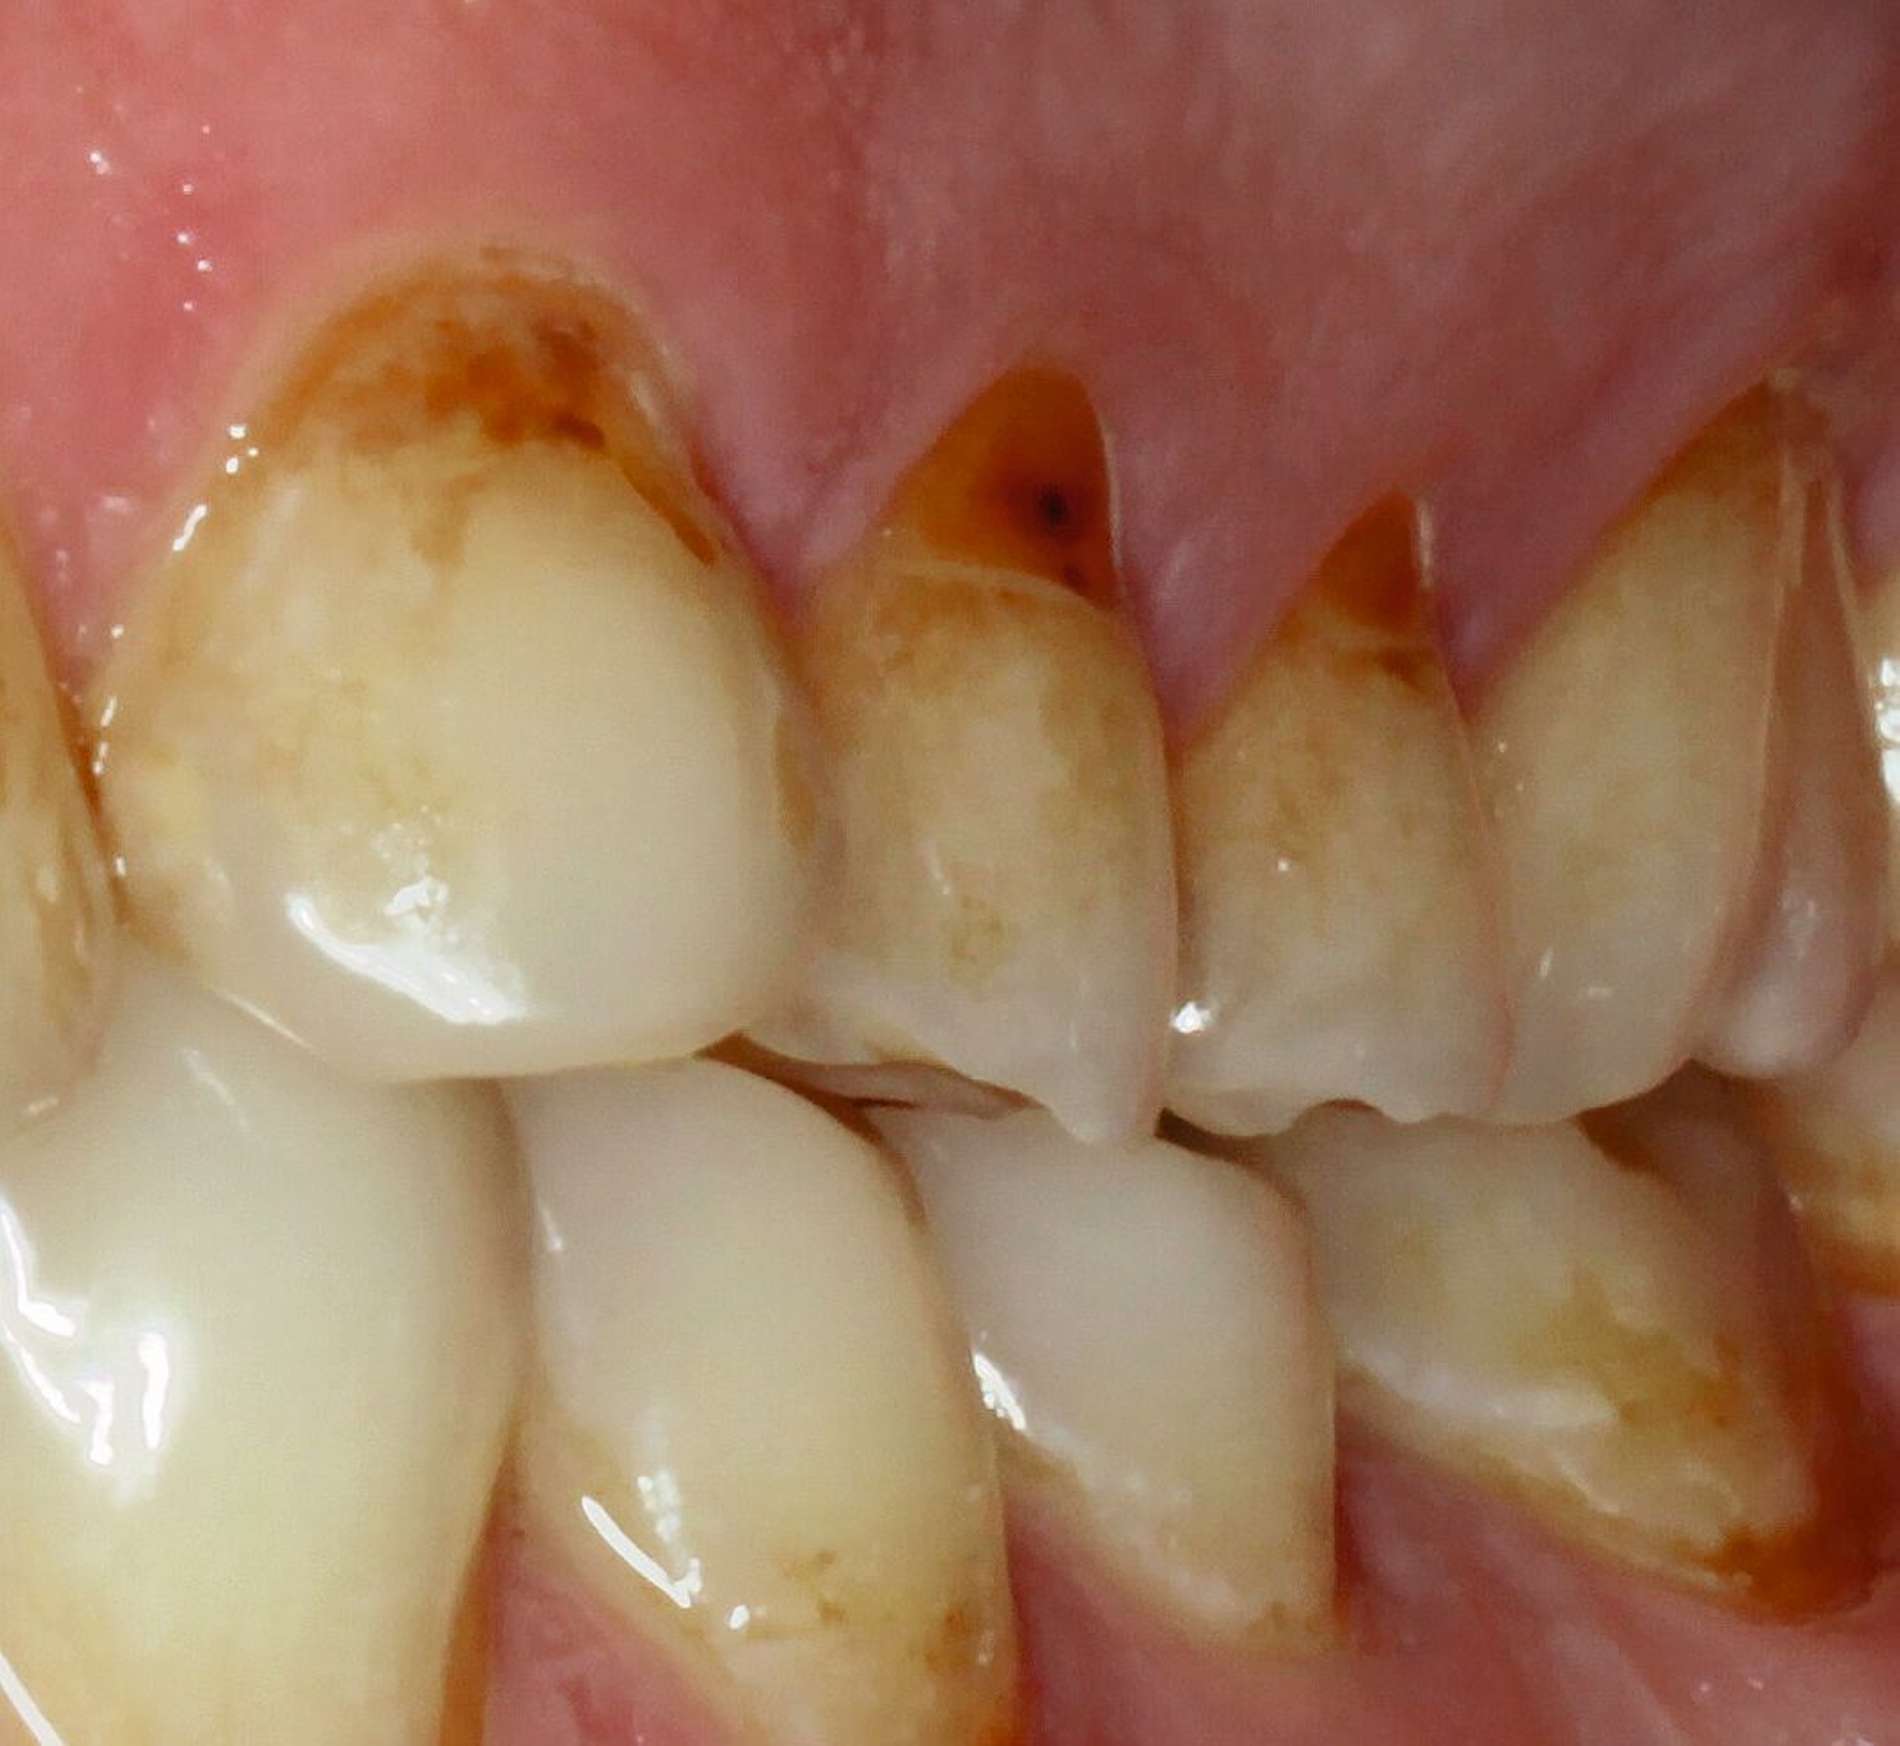

Diagnostik

Klinisch präsentierte sich ein vollbezahntes Gebiss ohne Weisheitszähne mit Defekten an der Zahnstruktur teilweise bis ins Dentin. Es waren deutliche Erosionsspuren zu erkennen, die auf die säurehaltige Ernährung im Kurzzeitintervall zurückgeführt wurden. Der BEWE-Index war mit dem Wert 13 auffällig und kategorisierte den Schaden als ausgeprägte Erosionen. Die Zähne 14, 13 und 24 wiesen nicht-kariöse zervikale Defekte auf, diese treten häufig im Zusammenhang mit Bruxismus auf [Pecie et al., 2011]. Das CMD-Screening der Deutschen Gesellschaft für Funktionsdiagnostik und -therapie (DGFDT) [DGFDT, 2024] war unauffällig, da der Patient über keinerlei Schmerzen oder Beschwerden bei Kieferbewegungen klagte. Die manuelle Strukturanalyse (MSA) nach Bumann [Fasold und Kordaß, 2012] ergab bei diesem Patienten ein myofaziales Schmerzsyndrom. Im Prämolarenbereich imponierten Zahnhartsubstanzdefekte, die Hinweise auf starkes und häufiges Zähnepressen geben. Den Patienten selbst störten seine kälteempfindlichen Zähne sowie die Gesamtästhetik aufgrund des massiven Substanzverlustes.